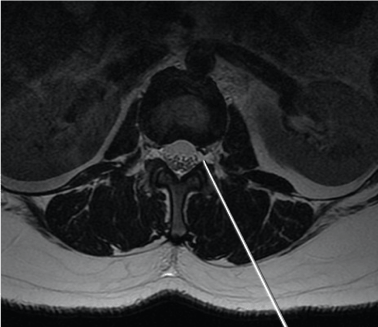

Findings on magnetic resonance imaging would include a subdural fluid collection, the MR signal characteristics of which depend on the age of the hematoma (Figures 7a, 7b, 7c). Acute hematoma which contains deoxyhemoglobin is iso- to hypointense on T1-weighted images and hypointense on T2-weighted images. Intracellular methemoglobin within early subacute hematoma is T1 hyperintense and T2 hypointense while extracellular methemoglobin within late subacute hematoma is hyperintense on both T1- and T2-weighted images.

Figure 7. (a)Sagittal T1 and (b) T2-weighted images of the lumbosacral spine show a late subacute subdural hematoma extending from the inferior border of the T12 vertebra to the level of S2. (c)Axial T1-weighted image again shows the late subacute haematoma within the lumbosacral spinal canal